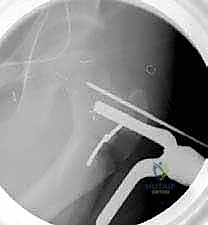

3. إدخال السلك الدليلي (Guide Wire)

تحت توجيه الأشعة السينية المباشرة داخل غرفة العمليات (C-arm)، يقوم الدكتور هطيف بإدخال سلك دليلي في عنق ورأس عظم الفخذ بالزاوية الصحيحة والمحسوبة بدقة.

6. التثبيت الداخلي القوي (Internal Fixation)

لضمان التحام العظم في وضعه الجديد، يستخدم الدكتور هطيف نظام تثبيت عالمي يتمثل في صفيحة الشفرة الزاوية (AO 90-degree Blade Plate) أو مسامير وصفيحة مخصصة للأطفال. يتم إدخال الشفرة في عنق الفخذ، وتثبيت الصفيحة على جسم العظم باستخدام براغي معدنية قوية.